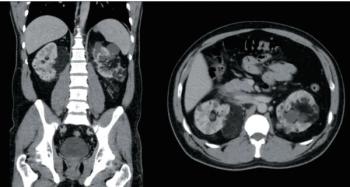

A 35-year-old man with a known history of tuberous sclerosis complex was referred to the urology clinic by his primary care physician for consultation regarding bilateral, multifocal renal masses.